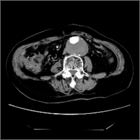

1. 腹部膨満・腹部腫瘤は腹腔内臓器の器質的病変に由来するものと機能的病態に起因するものがある。

1. 腹部膨満の原因は、①腸管内ガス・液体の過剰な貯留、②腸管外腹腔内の異常な気体・液体貯留、③腹腔内臓器の腫大・腫瘤、④肥満、⑤妊娠――など多岐にわたる。